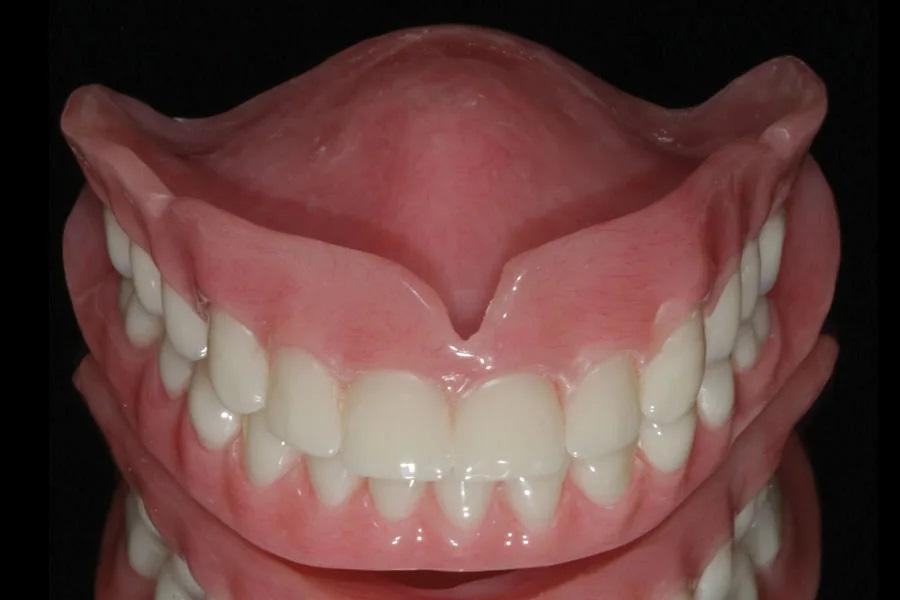

Процесс изготовления переходных и окончательных зубных протезов был начат с помощью 3D-интраорального оптического сканирования в середине февраля 2020 года и завершен во время пандемии COVID, когда в начале марта 2021 года были доставлены окончательные зубные протезы (Фото 8 и Фото 9). Пациентка посещала кабинет врача в общей сложности 10 раз, включая два отдельных хирургических визита (по одному на каждую дугу) и все послеоперационные и корректирующие визиты. Это также включало в себя изготовление и поставку временных зубных протезов, заживление мягких и твердых тканей, функциональные оттиски и поставку окончательных зубных протезов. Для сравнения, традиционное поэтапное удаление боковых зубов, регистрация данных и обычные слепки для временных протезов привели бы к гораздо большему количеству посещений, и пациентке пришлось бы длительное время терпеть неудобства, связанные с отсутствием большинства зубов, пока изготавливались временные протезы.

Фото 8: Окончательные протезы.